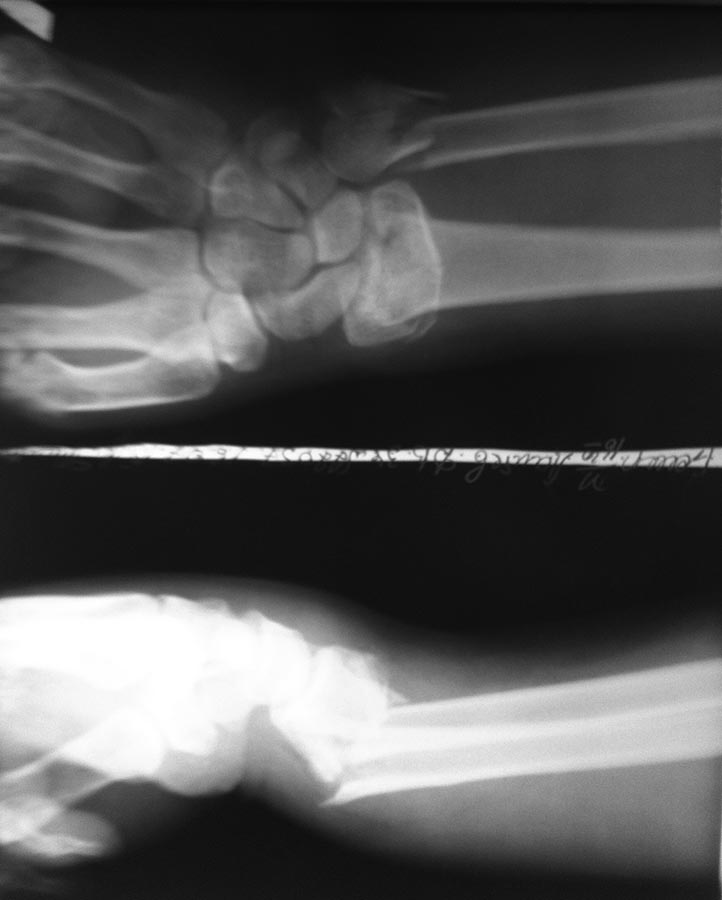

Здравствуйте, Александр Николаевич! Такой вариант я, находясь у Вас на учебе, видел и рассматривал. Но у меня перелом лучевой кости внутрисуставной и локтевая сломана. В итоге то, что придумалось мне показалось приемлемее.

Р-грамма после репозиции.

Здравствуйте,по снимкам неплохо. А какая причина отказа от открытой репозиции, остеосинтеза пластинами? Финансовая? Сохраняется смещение отломка Локтевой кости с диастазом между отломками. Не критично? Может наступить замедленная консолидация..